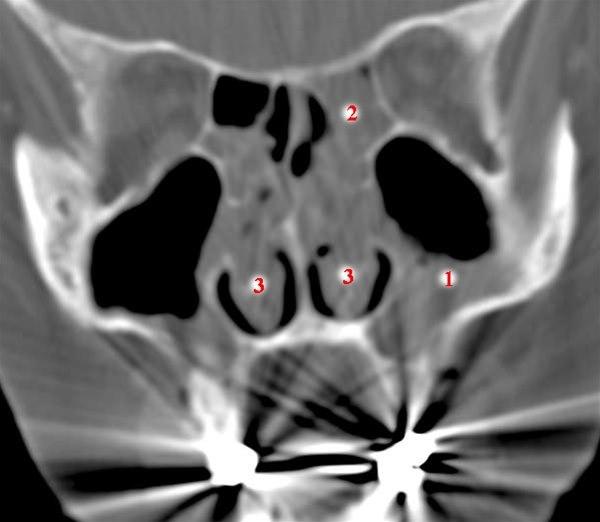

Ved uklarhet om diagnosen kan en CT-undersøkelse avklare om det foreligger polypper og kartlegge omfanget av polyppene. Dersom du henvises til spesialist, vil ØNH-legen undersøke nesen innvendig, ofte ved hjelp av et endoskop. I samme seanse kan ØNH-legen om ønskelig også fjerne polyppene gjennom endoskopet.